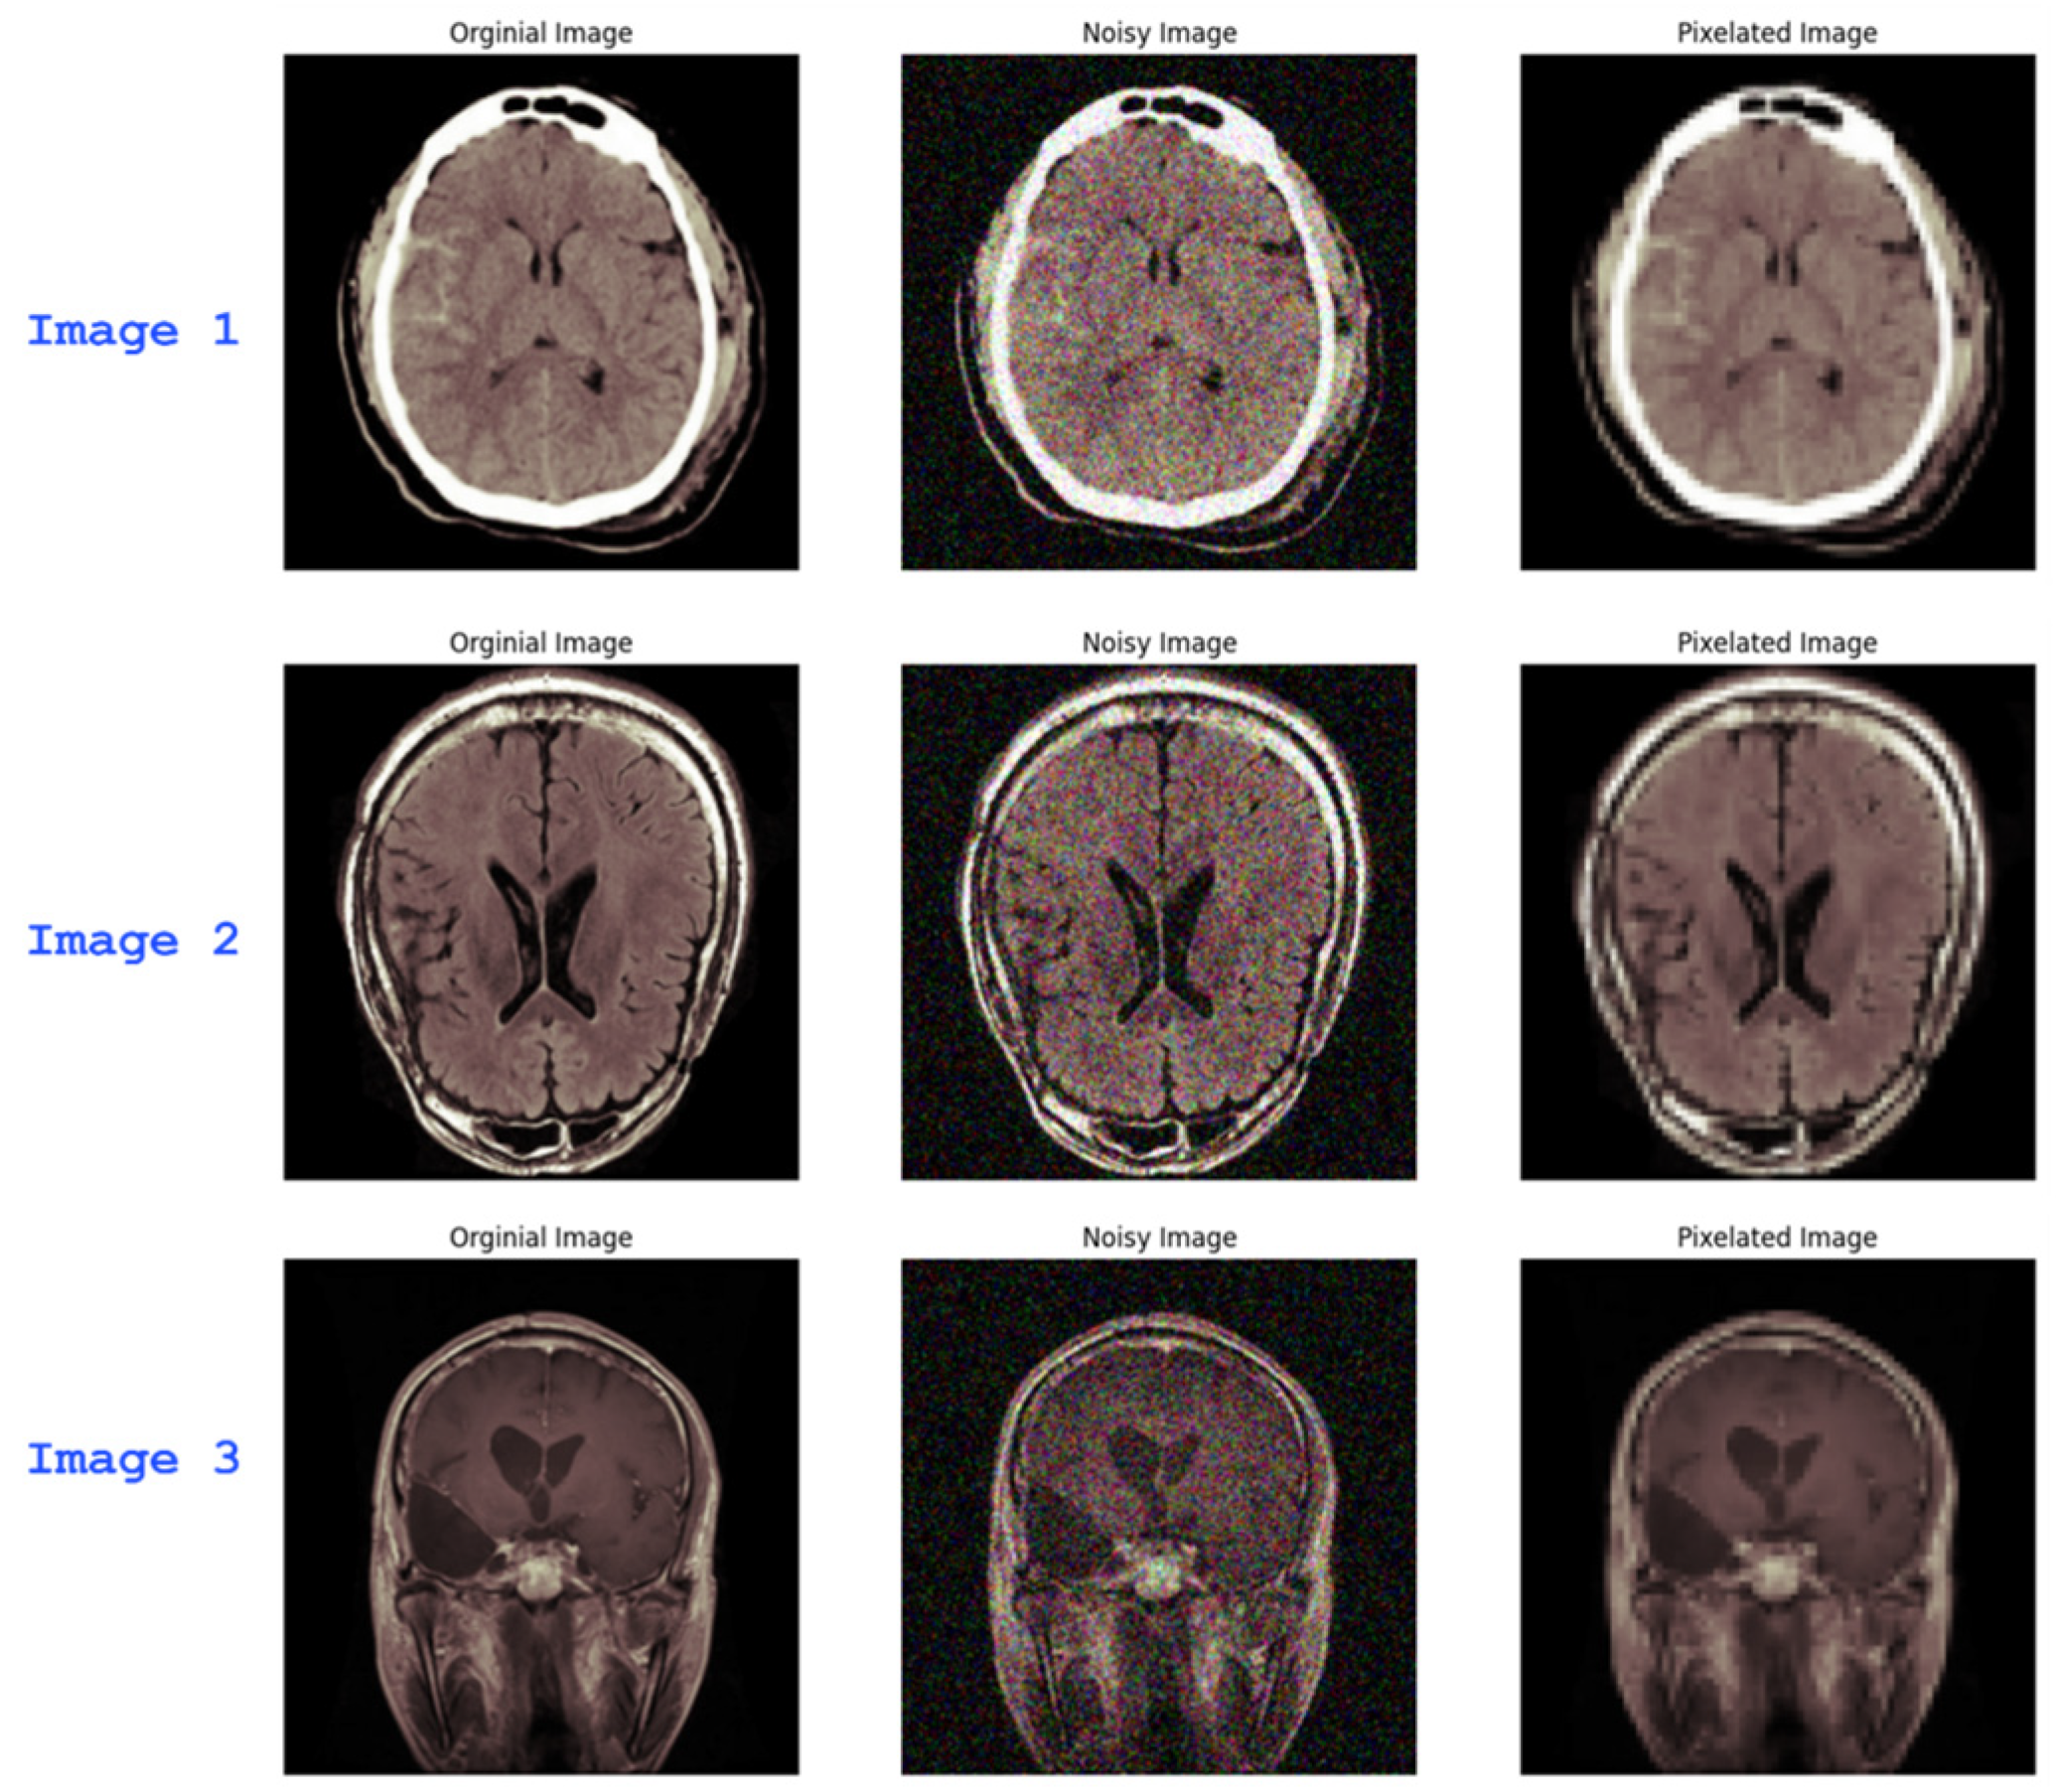

2.3. Noise and Blur Introduction

2.3. Autoencoders for Noise and Blur Mitigation